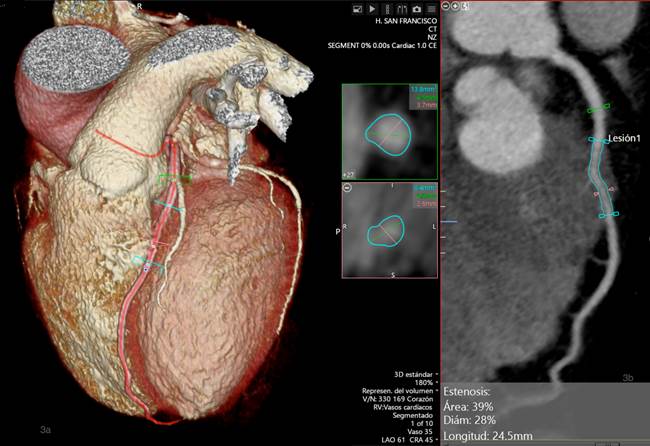

Para la estimación de la estenosis, se comparó el área más estrecha del segmento puenteado con el área del segmento previo al PM en vista MPR curvado, obteniendo una estenosis del 56% en sístole (fase 40%) y 39% en diástole (fase 0%) (Figs. 2 y 3).